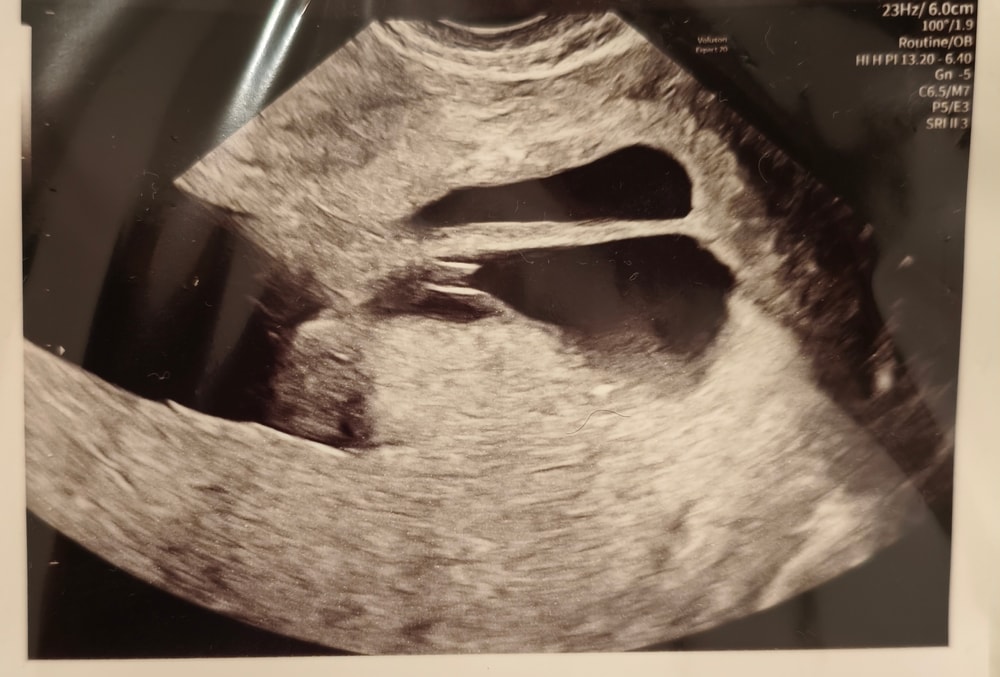

Вчера на УЗИ обнаружили перегородку в матке.

Приложу изображение с УЗИ, может кто-то разбирается 😭